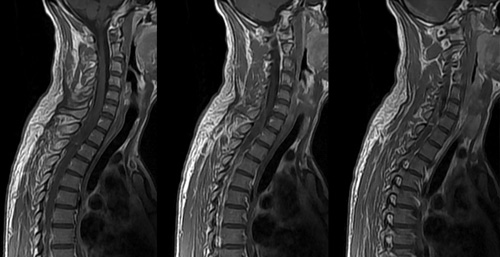

Po lewej: MRI kolana. Po prawej: wizualizacja wielkości cząstek złogów stawowych, które przedostają się do krwiobiegu.